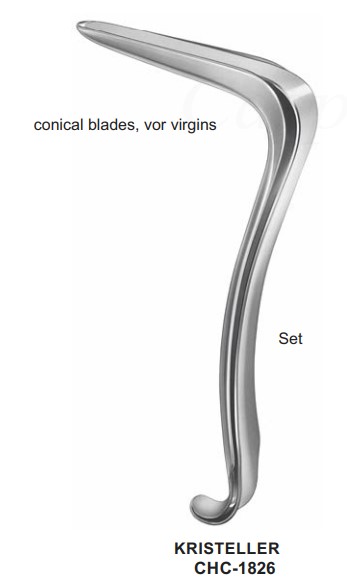

CHC-1826 | Gynecology |